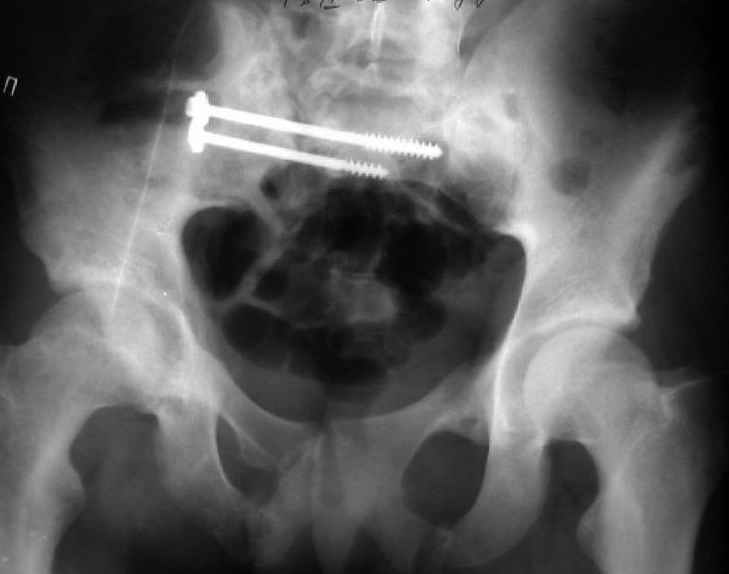

Для информации к размышлению о возможности исправления имеющейся деформации предлагаю похожий случай.